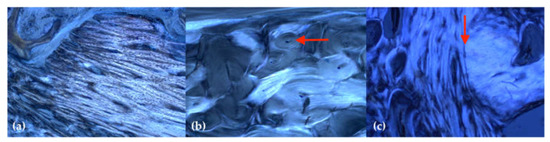

2.3. Histology

- Hahn, M.; Vogel, M.; Delling, G. Undecalcified preparation of bone tissue: Report of technical experience and development of new methods. Virchows Arch. A Pathol. Anat. 1991, 418, 1–7. [Google Scholar] [CrossRef]